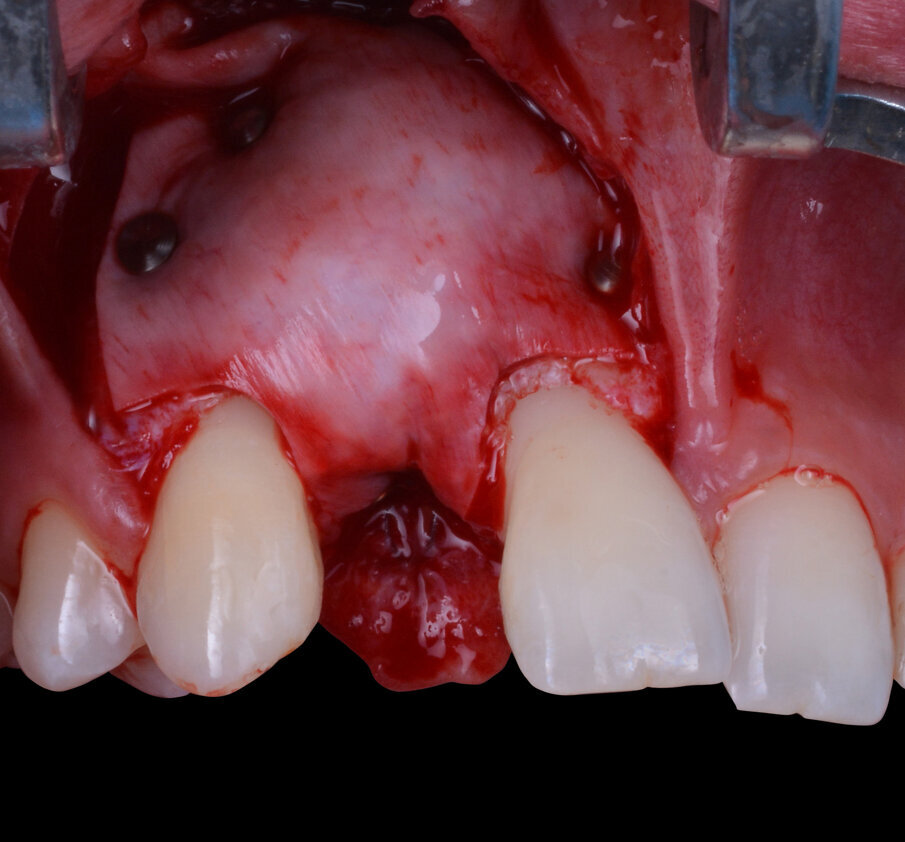

La fase chirurgica successiva consiste nella scheletrizzazione del sito da trattare così da rendere visivamente evidente quanto già evinto dallo studio preliminare, ovvero una moderata carenza ossea della regione vestibolare del processo alveolare (Fig. 5). La scelta della sistematica implantare da utilizzare ricade sull’impianto endo-osseo “Nobel Biocare Replace Conical Connection”. La strumentazione osteotomica iniziale viene eseguita sotto abbondante irrigazione di acqua fisiologica sterile refrigerata e, dopo una accurata preparazione con una fresa inziale lanceolata, una fresa del diametro di 2,0 mm e un’ultima del diametro di 3,5 mm si procede con l’inserimento di un impianto del diametro di 3,5 mm per 11,5 di lunghezza. Con l’avvitamento dell’impianto all’interno del tunnel osteotomico precedentemente ottenuto si raggiunge un torque di inserzione di circa 30 N/cm2, valore in grado di garantire una fisiologica guarigione del sito trattato.

Ad inserimento della fixture avvenuto si rileva la presenza di una piccola fenestrazione vestibolare classificabile come un’atrofia vestibolare di Classe II secondo la classificazione di Chiapasco e Casentini dei difetti ossei perimplantari del 20188 (Fig. 6). La tecnica chirurgica scelta per la gestione del difetto osseo è la GBR. Il primo step contempla di eseguire dei fori di osteopromozione sulla corticale vestibolare attraverso uno strumento rotante a basso numero di giri e senza ausilio di irrigazione con acqua fisiologica così da ottenere un maggior apporto ematico endostale nella regione da trattare e la successiva aggiunta di particolato di osso autologo che conferisca osteoinduttività e osteogeneticità all’innesto (Fig. 7). Il difetto viene gestito impiegando scaffold inorganici, ovvero dei biomateriali che fungono da riempitivi inerti con proprietà osteoconduttive (in grado di guidare la rigenerazione ossea facilitando la stratificazione e l’organizzazione del coagulo su di essi) e di space making (capaci di mantenere lo spazio necessario alla rigenerazione impedendo il collasso parziale o totale dei tessuti molli sovrastanti)9. Nel caso specifico, il biomateriale eterologo innestato è di origine bovina (Nobel Biocare Xenogain 0,2-1 mm); dopo l’accurato posizionamento del biomateriale nella regione da trattare si procede alla protezione dello stesso con una membrana riassorbibile in pericardio bovino con matrice tridimensionale (Ubgen, Shelter/sistema Pericross) stabilizzata per mezzo di pins di fissazione sia palatalmente che vestibolarmente (Fig. 8). L’esecuzione di un’incisione di rilascio periostale del lembo vestibolare permette di ottenere una chiusura per prima intenzione della ferita caratterizzata da una competente interfaccia dei due lembi e da una passivazione degli stessi (Fig. 9). La dimissione della paziente avviene solo dopo aver applicato con cementazione adesiva il Maryland bridge provvisorio prestando particolarmente attenzione a evitare compressioni sui tessuti molli appena trattati chirurgicamente. Durante il periodo di guarigione la paziente viene rivalutata con cadenza mensile per controllare il procedere del fisiologico decorso post-operatorio. A 6 mesi dall’inserimento dell’impianto, dopo opportuni controlli radiografici, si procede con la programmazione della riapertura.

Fig. 7 - Osso autologo particolato ottenuto durante l’esecuzione di fori di osteopromozione.

Fig. 8 - Stabilizzazione del complesso innesto-membrana.